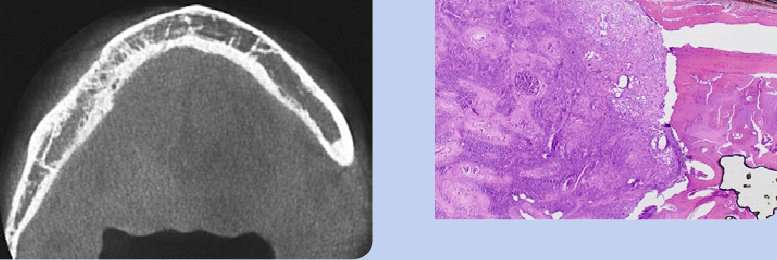

Bei einem 65-jährigen Patienten und Raucher wurde im Juli 2014 ein Plattenepithelkarzinom, T2, N0, diagnostiziert. Die klinische Untersuchung ergab eine ulzerierende, nekrotisierende Läsion im IV. Quadranten mit Verdacht auf knöcherne Infiltration eines Plattenepithelkarzinomrezidivs (Abb. 10 u. 11). Die radiologische Diagnostik legte die Vermutung einer Tumorinfiltration der UK-Kompakta und der Spongiosa nahe (Abb. 12–16). Diagnose: ein invasives, ulzeriertes und mäßig differenziertes Plattenepithelkarzinom, pT4a, G2.